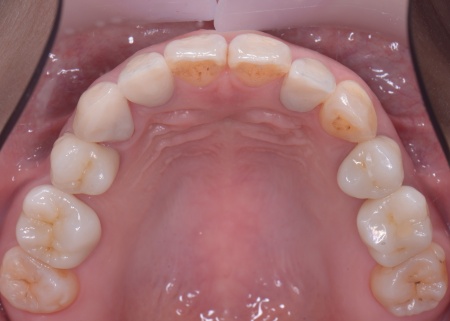

| カウンセリング | 拝見したところ、左下と右上の歯はともに大きな虫歯があり、歯だけでなく被せ物を支える土台の部分にも影響が及んでいました。

さらに、ほかの歯に入っている詰め物や被せ物の周囲にも、過去に治療した部分に再び虫歯ができる二次カリエスが複数見つかりました。 また、噛み合わせを確認したところ、奥歯で噛み合わせた際に上下の前歯が当たらず隙間ができる開咬(かいこう)が認められました。 実際に患者様の場合も、特定の歯に長期間強い力がかかり続けたことで歯や修復物の破損、さらには口腔内全体のトラブルにつながった可能性が高いと考えられました。 修復治療が必要でしたがこの噛み合わせの問題を改善しないまま行うと、治療した歯に再び過度な力が加わって被せ物の破損・脱離や虫歯の再発を招くリスクが高まります。 |

まずは矯正治療を優先し、噛み合わせが整ってから虫歯の再発リスクの低いセラミックの被せ物・詰め物などで歯の形態と機能を回復する方針を提案し、同意いただきました。

矯正治療については、専門的な診断と管理が必要と判断したため専門の矯正歯科医院をご紹介し、他院にて実施していただきました。 矯正治療終了後、改めてお口の中を確認したうえで、歯の状態に合わせ虫歯の除去や土台の修復を丁寧に行い、精密な型取りを実施しています。 最後に噛み合わせ全体のバランスを確認しながら新しく作製した被せ物や詰め物を装着し、見た目に問題がないか、噛み合わせが安定しているかを確認し、治療を終了しました。 |